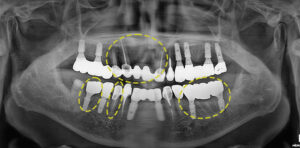

먼저 심한 염증으로 인해 살려서

사용할 수 없는 앞니는 발치를 진행하고

나머지 보존 가능한 치아들은 브릿지로

연결하여 자연 치아를 사용하기로 하였어요.

왼쪽 아래 어금니들은 이미 보존치료의 마지막

수단이었던 신경치료도 진행되어 있는 상태이며,

잔존 치관도 거의 남아있지 않고 염증으로 인해

흔들림도 심한 상태라 발치 후 임플란트를

진행하기로 하였어요.

반대쪽 어금니들도 마찬가지로

신경치료가 되어있는 치아는

살리기 어려울 것으로 보여 발치 후

임플란트를 하기로 계획하였고,

앞 쪽 작은 어금니는 충치 제거 후

증상을 파악하여 보철치료로

치아를 보존하여 사용하기로 하였어요.

먼저 임플란트 전체적으로 발치가 필요한 치아들을

제거한 후 임플란트를 식립해 주었어요.👏

염증으로 인해 잇몸뼈가 부족한 부분은

뼈이식도 추가로 진행했는데요.